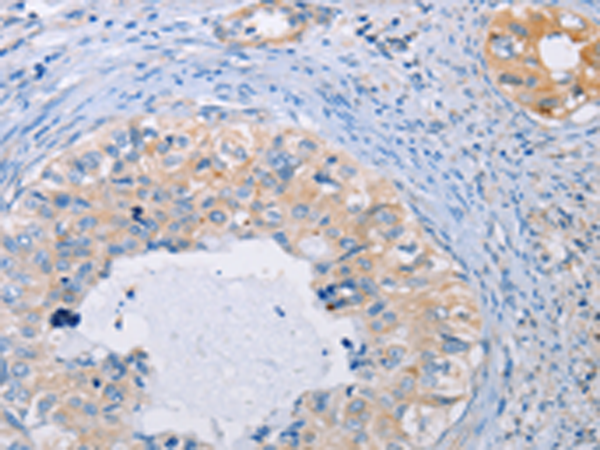

分类: 科研抗体货号: P07781别名: M12.219应用: IHC反应种属: Human